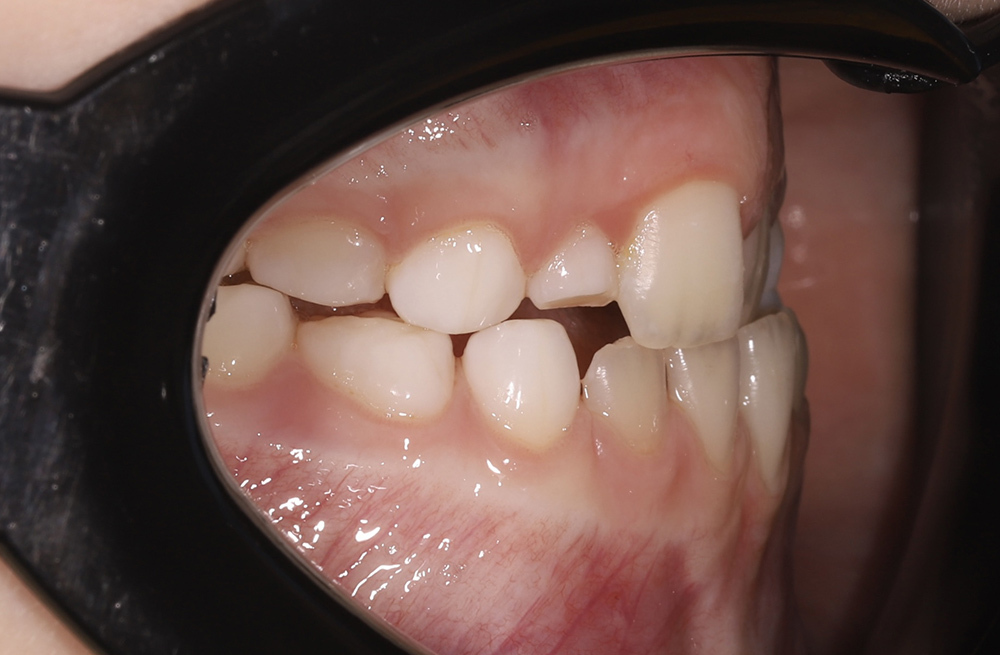

Примеры работ